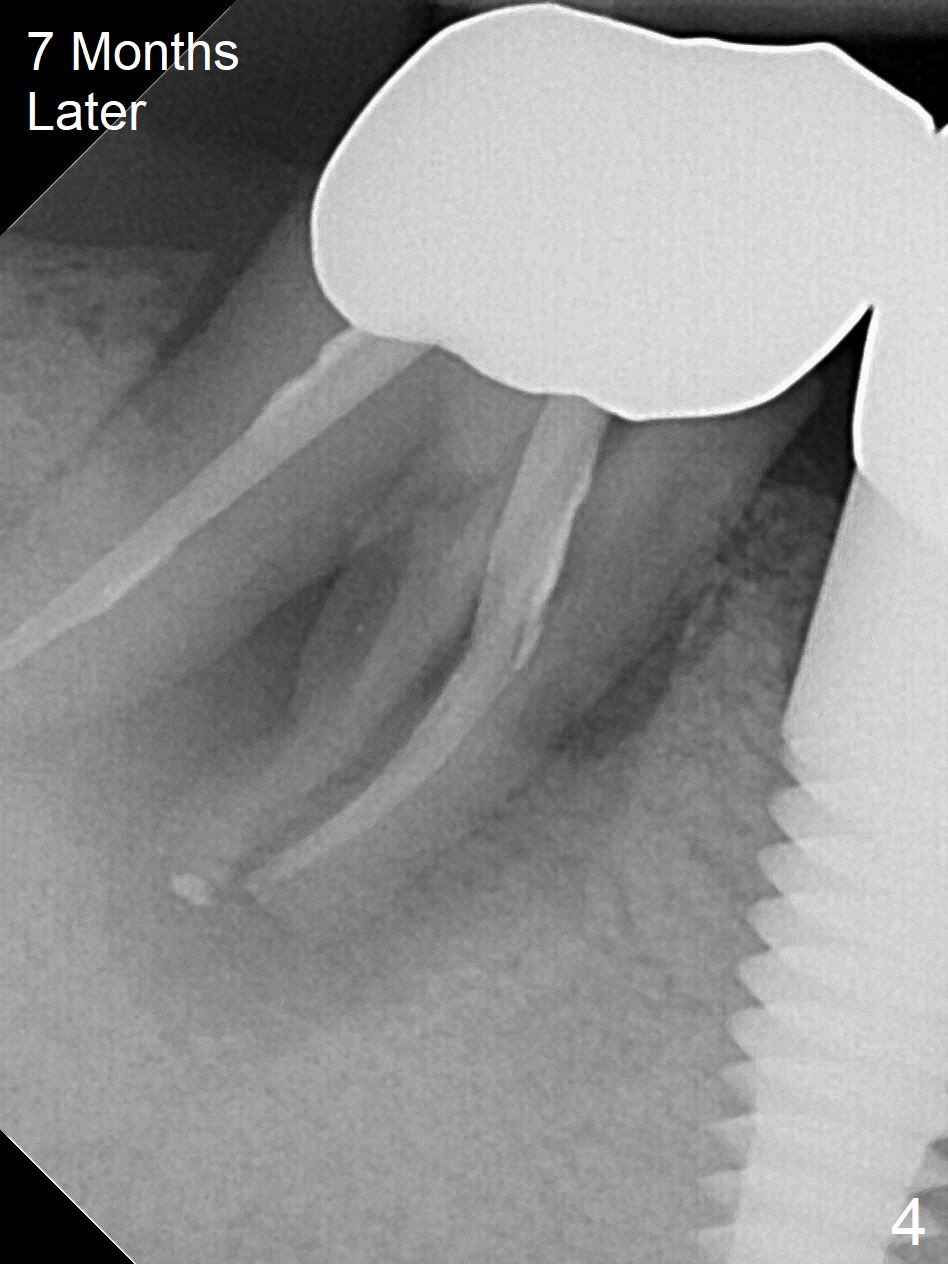

A 87-year-old man was asymptomatic with the tooth #31 eight months earlier (Fig.1), as compared to now (Fig.2). After extraction, osteotomy will be initiated in the septum (where there is more bone height) using IS 6 mm stopper (Fig.3 red line), followed by PA. If PA does not show the Inferior Alveolar Canal (Fig.1 red dashed line), take panoramic X-ray. A 5.5x13 mm implant will be placed (7 mm may not be covered by the native bone). The mesial root vertical root fracture is more obvious 7 months later (Fig.4,5).